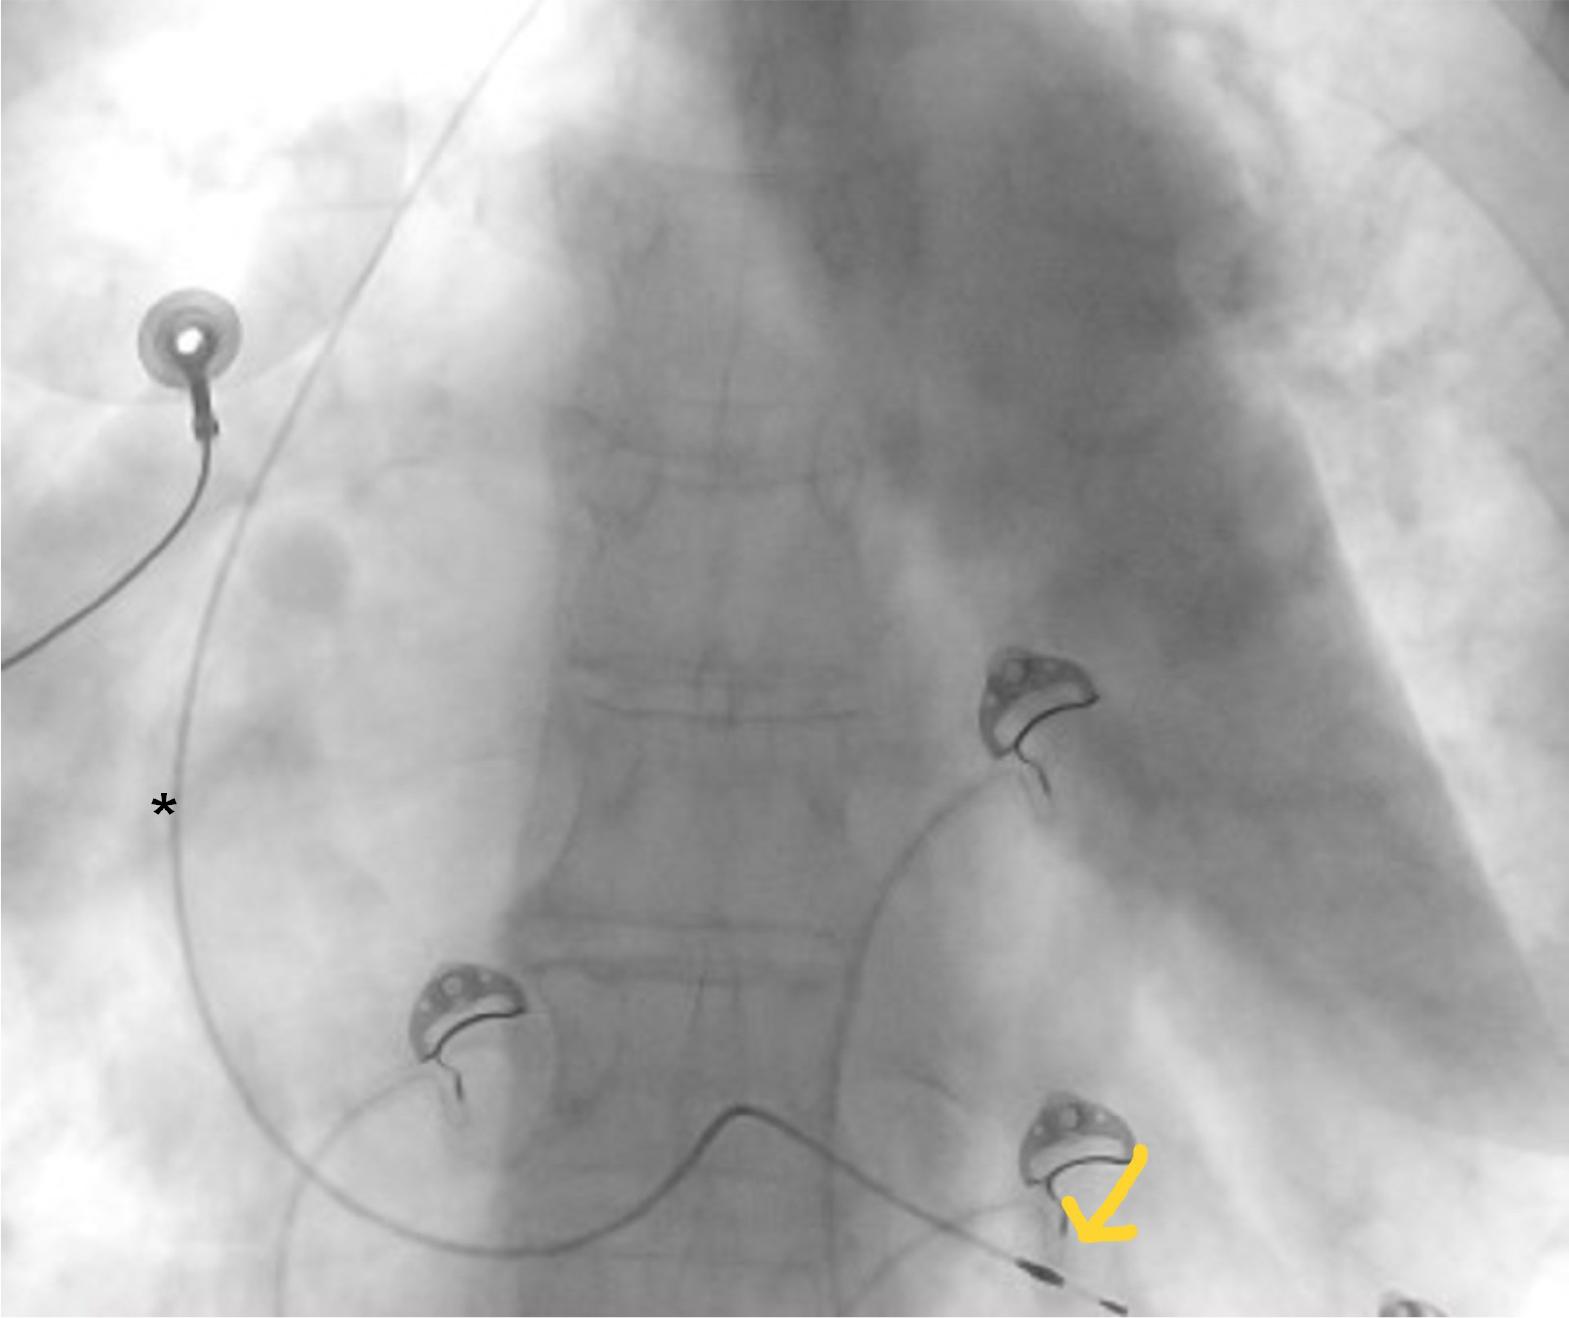

Initially, multiple attempts were made through left cephalic approach to position a lead with active fixation at the level of the right ventricular apex, but because of the modified cardiac anatomy, atrioventricular valve regurgitations, and high intracardiac pressures, this approach could not be used. During the procedure, the patient experienced multiple episodes of ventricular fibrillation, which stopped spontaneously, caused by myocardial irritation due to the immediately dislodging lead. In the context of the unavailability of a leadless lead, a surgical placement attempt of an epicardial lead was discussed in the heart team. However, the surgical risk was considered prohibitive due to severe pulmonary hypertension. The transvenous approach was attempted in a second procedure, and we managed to place a pacing lead with passive fixation at the right ventricle apex which proved stable, the positioning of the passive lead particularly facilitated by the trabeculated myocardium (Figure 4). Acute parameters for stimulation and sensing were RV = 0.5V/0.6ms/5.6mV, RV impedance = 900 ohms. The pacemaker was programmed in VVI mode, with a base rate of 50 beats per minute and hysteresis set to 40 beats per minute.

Postero-anterior chest X-ray showing the positioning of the pacemaker lead (*).